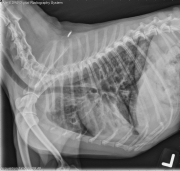

This week’s case is a 6-year-old male neutered Chihuahua with chronic cough that has not responded to therapy. What are your radiographic findings?

R LAT Thorax

There is a severe, diffuse bronchial pattern throughout the lungs. The bronchial walls are thickened and do not taper appropriately in the periphery. There is alveolar pattern in the dependent portion of the right middle lung lobe, and interstitial to alveolar pattern in the dependent left cranial lung lobe. The cardiovascular structures are normal in size. There is a mild redundant tracheal membrane. The portion of the abdomen included is normal.

• Bronchitis with bronchiectasis (bacterial, eosinophilic)

• Secondary pneumonia or fibrosis ventrally

• Eosinophilic bronchopneumopathy

• Peripheral and airway eosinophilia

The cough resolved with antibiotic therapy, nebulization, and oral prednisone.